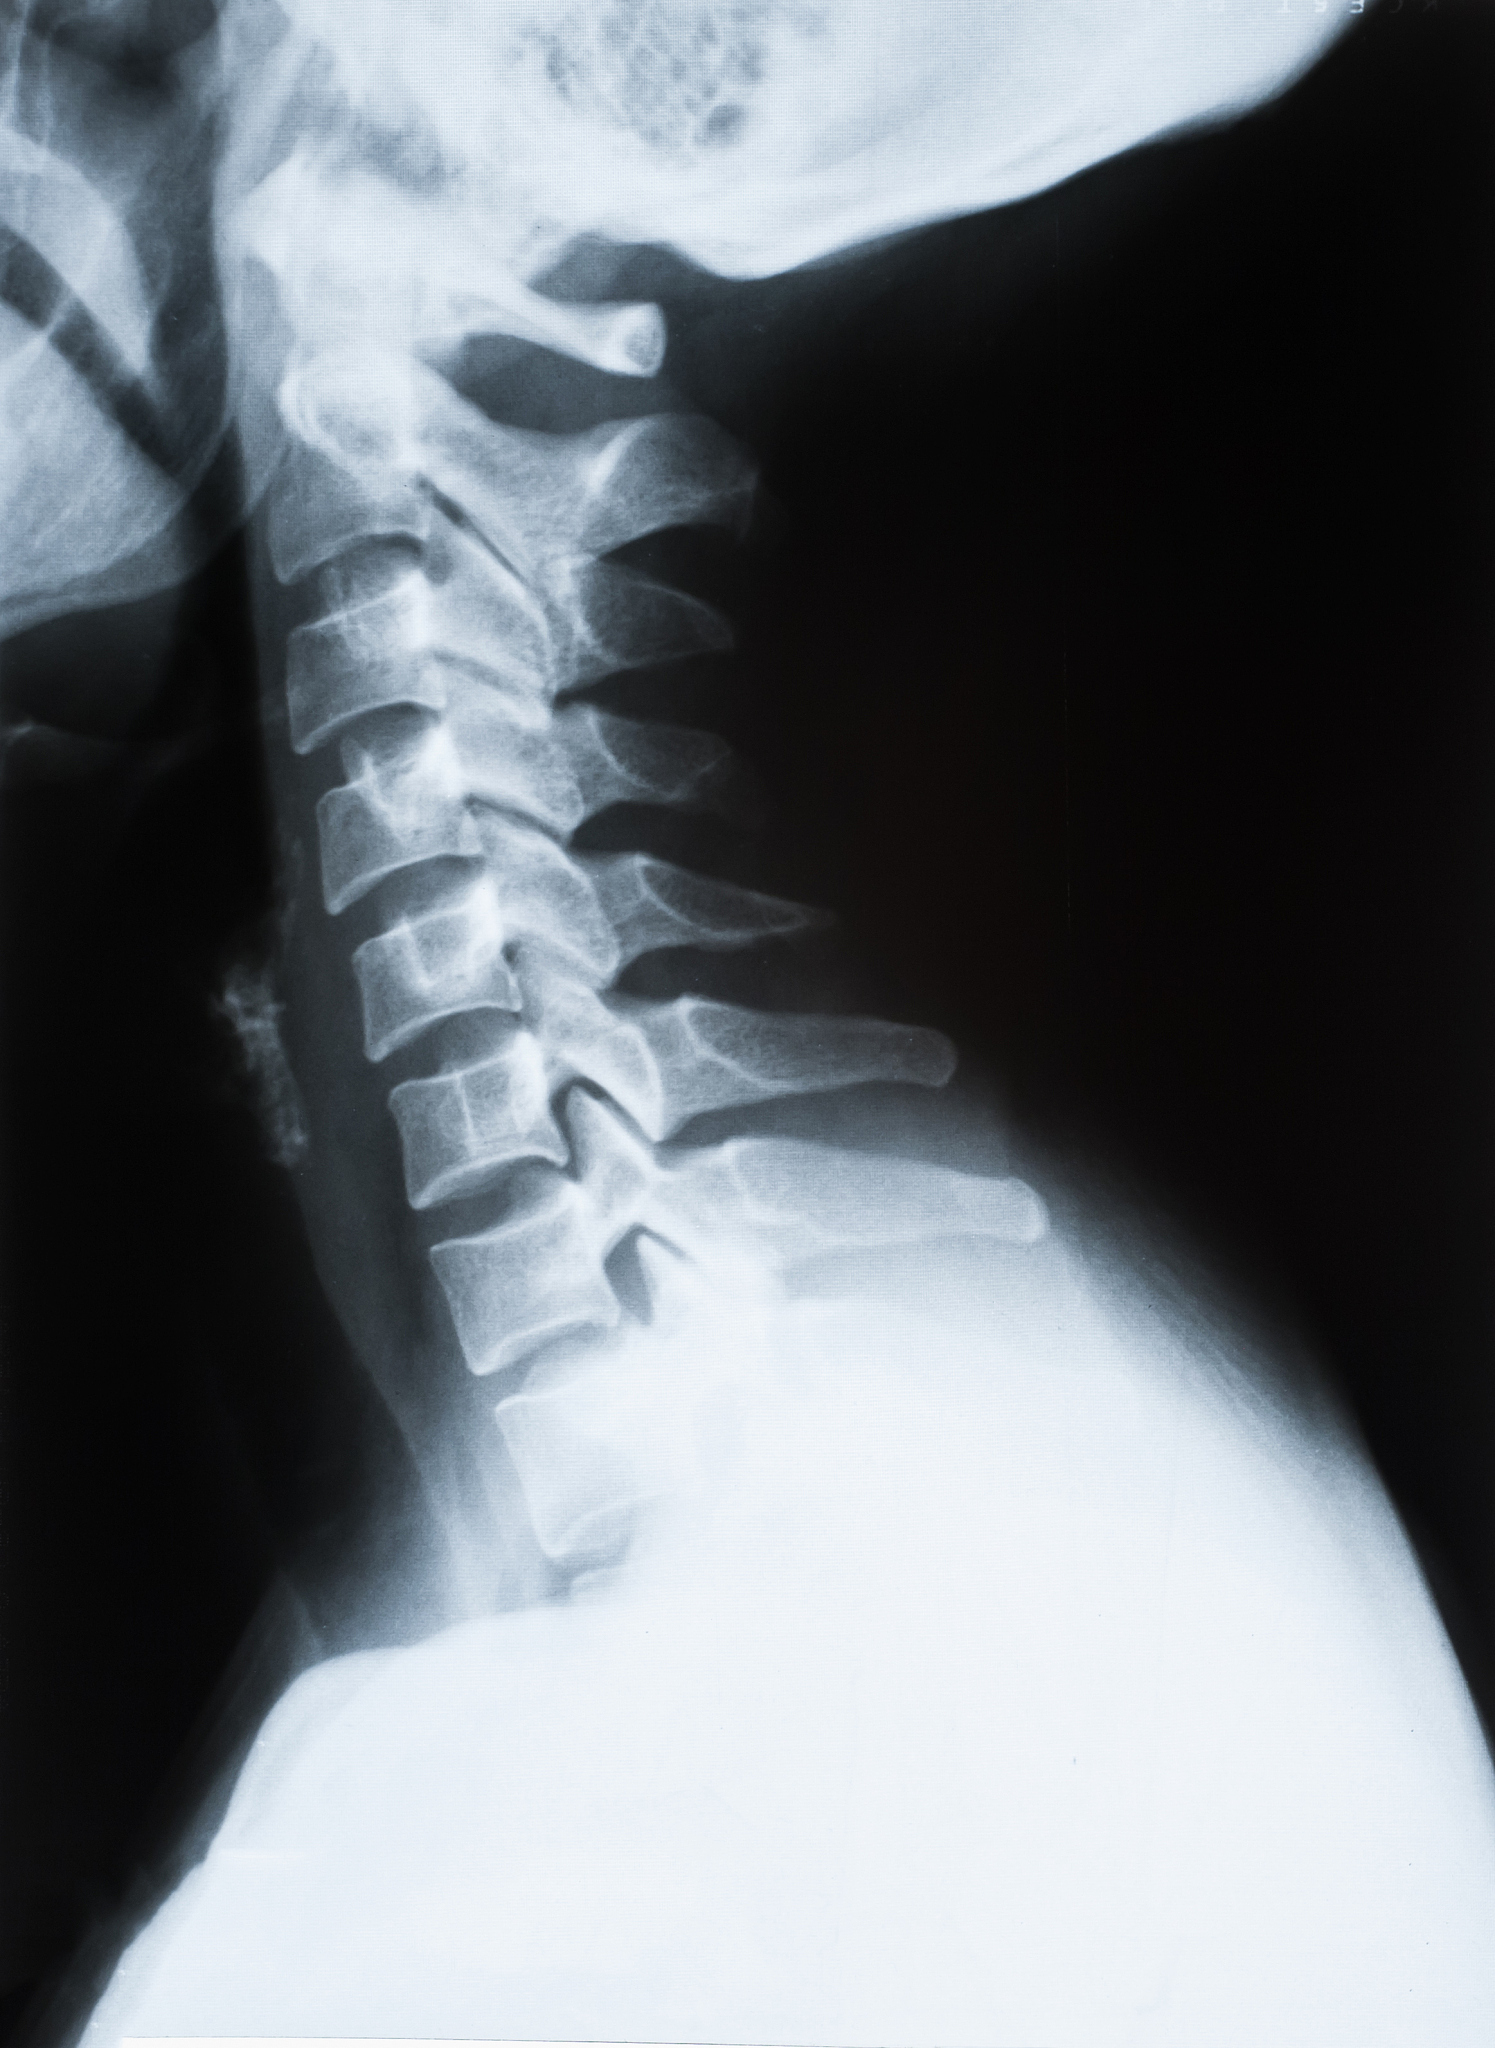

30. 颈椎病的基本病因是( ) B. 颈椎间盘退行性变